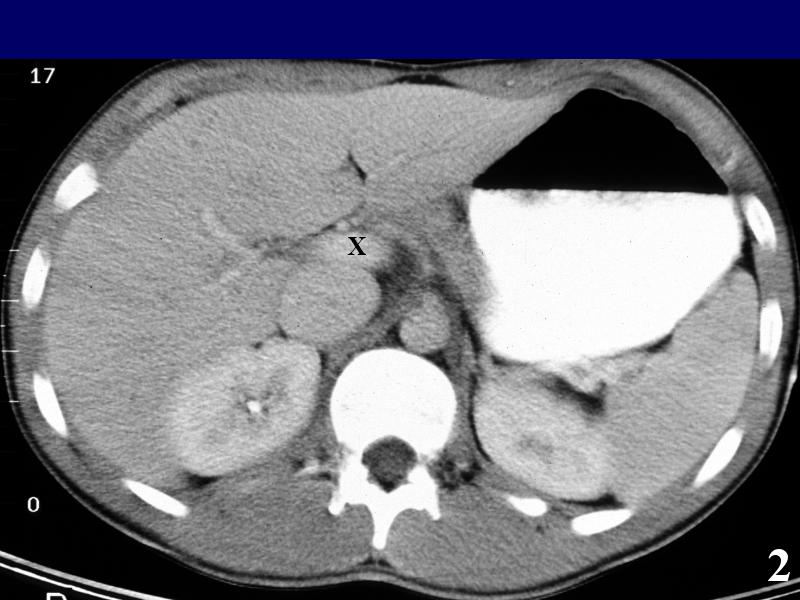

MS 190 CT 13